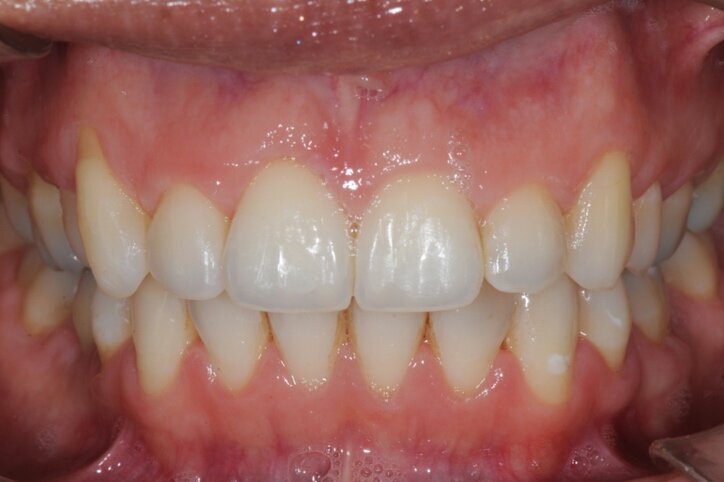

Figg. 6a-6d - Foto intraorali post-trattamento: visioni frontale (a), laterali (b), occlusali (c, d).

In questo modo è stato possibile ottimizzare i tempi, impiegando il periodo dell’ossointegrazione per completare la terapia ortodontica. Ulteriore ottimizzazione dei tempi è stata possibile rimuovendo, un mese prima del termine della terapia ortodontica, gli “engagers” ed utilizzando gli allineatori come “carriers” per un gel sbiancante (Opalescence PF 10% - Ultradent Products Inc – South Jordan, Utah, USA) applicato dalla paziente nelle ore notturne (circa 8 ore al giorno) per 12 notti consecutive, al termine delle quali il risultato è apparso soddisfacente. Al termine della terapia ortodontica sono state rilevate le impronte in polivinilsilossano per la realizzazione della corona in posizione 4.6. Dato lo spazio mesiodistale ridotto, si è proceduto con la realizzazione di una corona di dimensioni corrispondenti ad un premolare (Figg. 6a-7). Al termine delle procedure protesiche sono state realizzate due mascherine di contenzione ed è stato prescritto il loro impiego solo per le ore notturne.